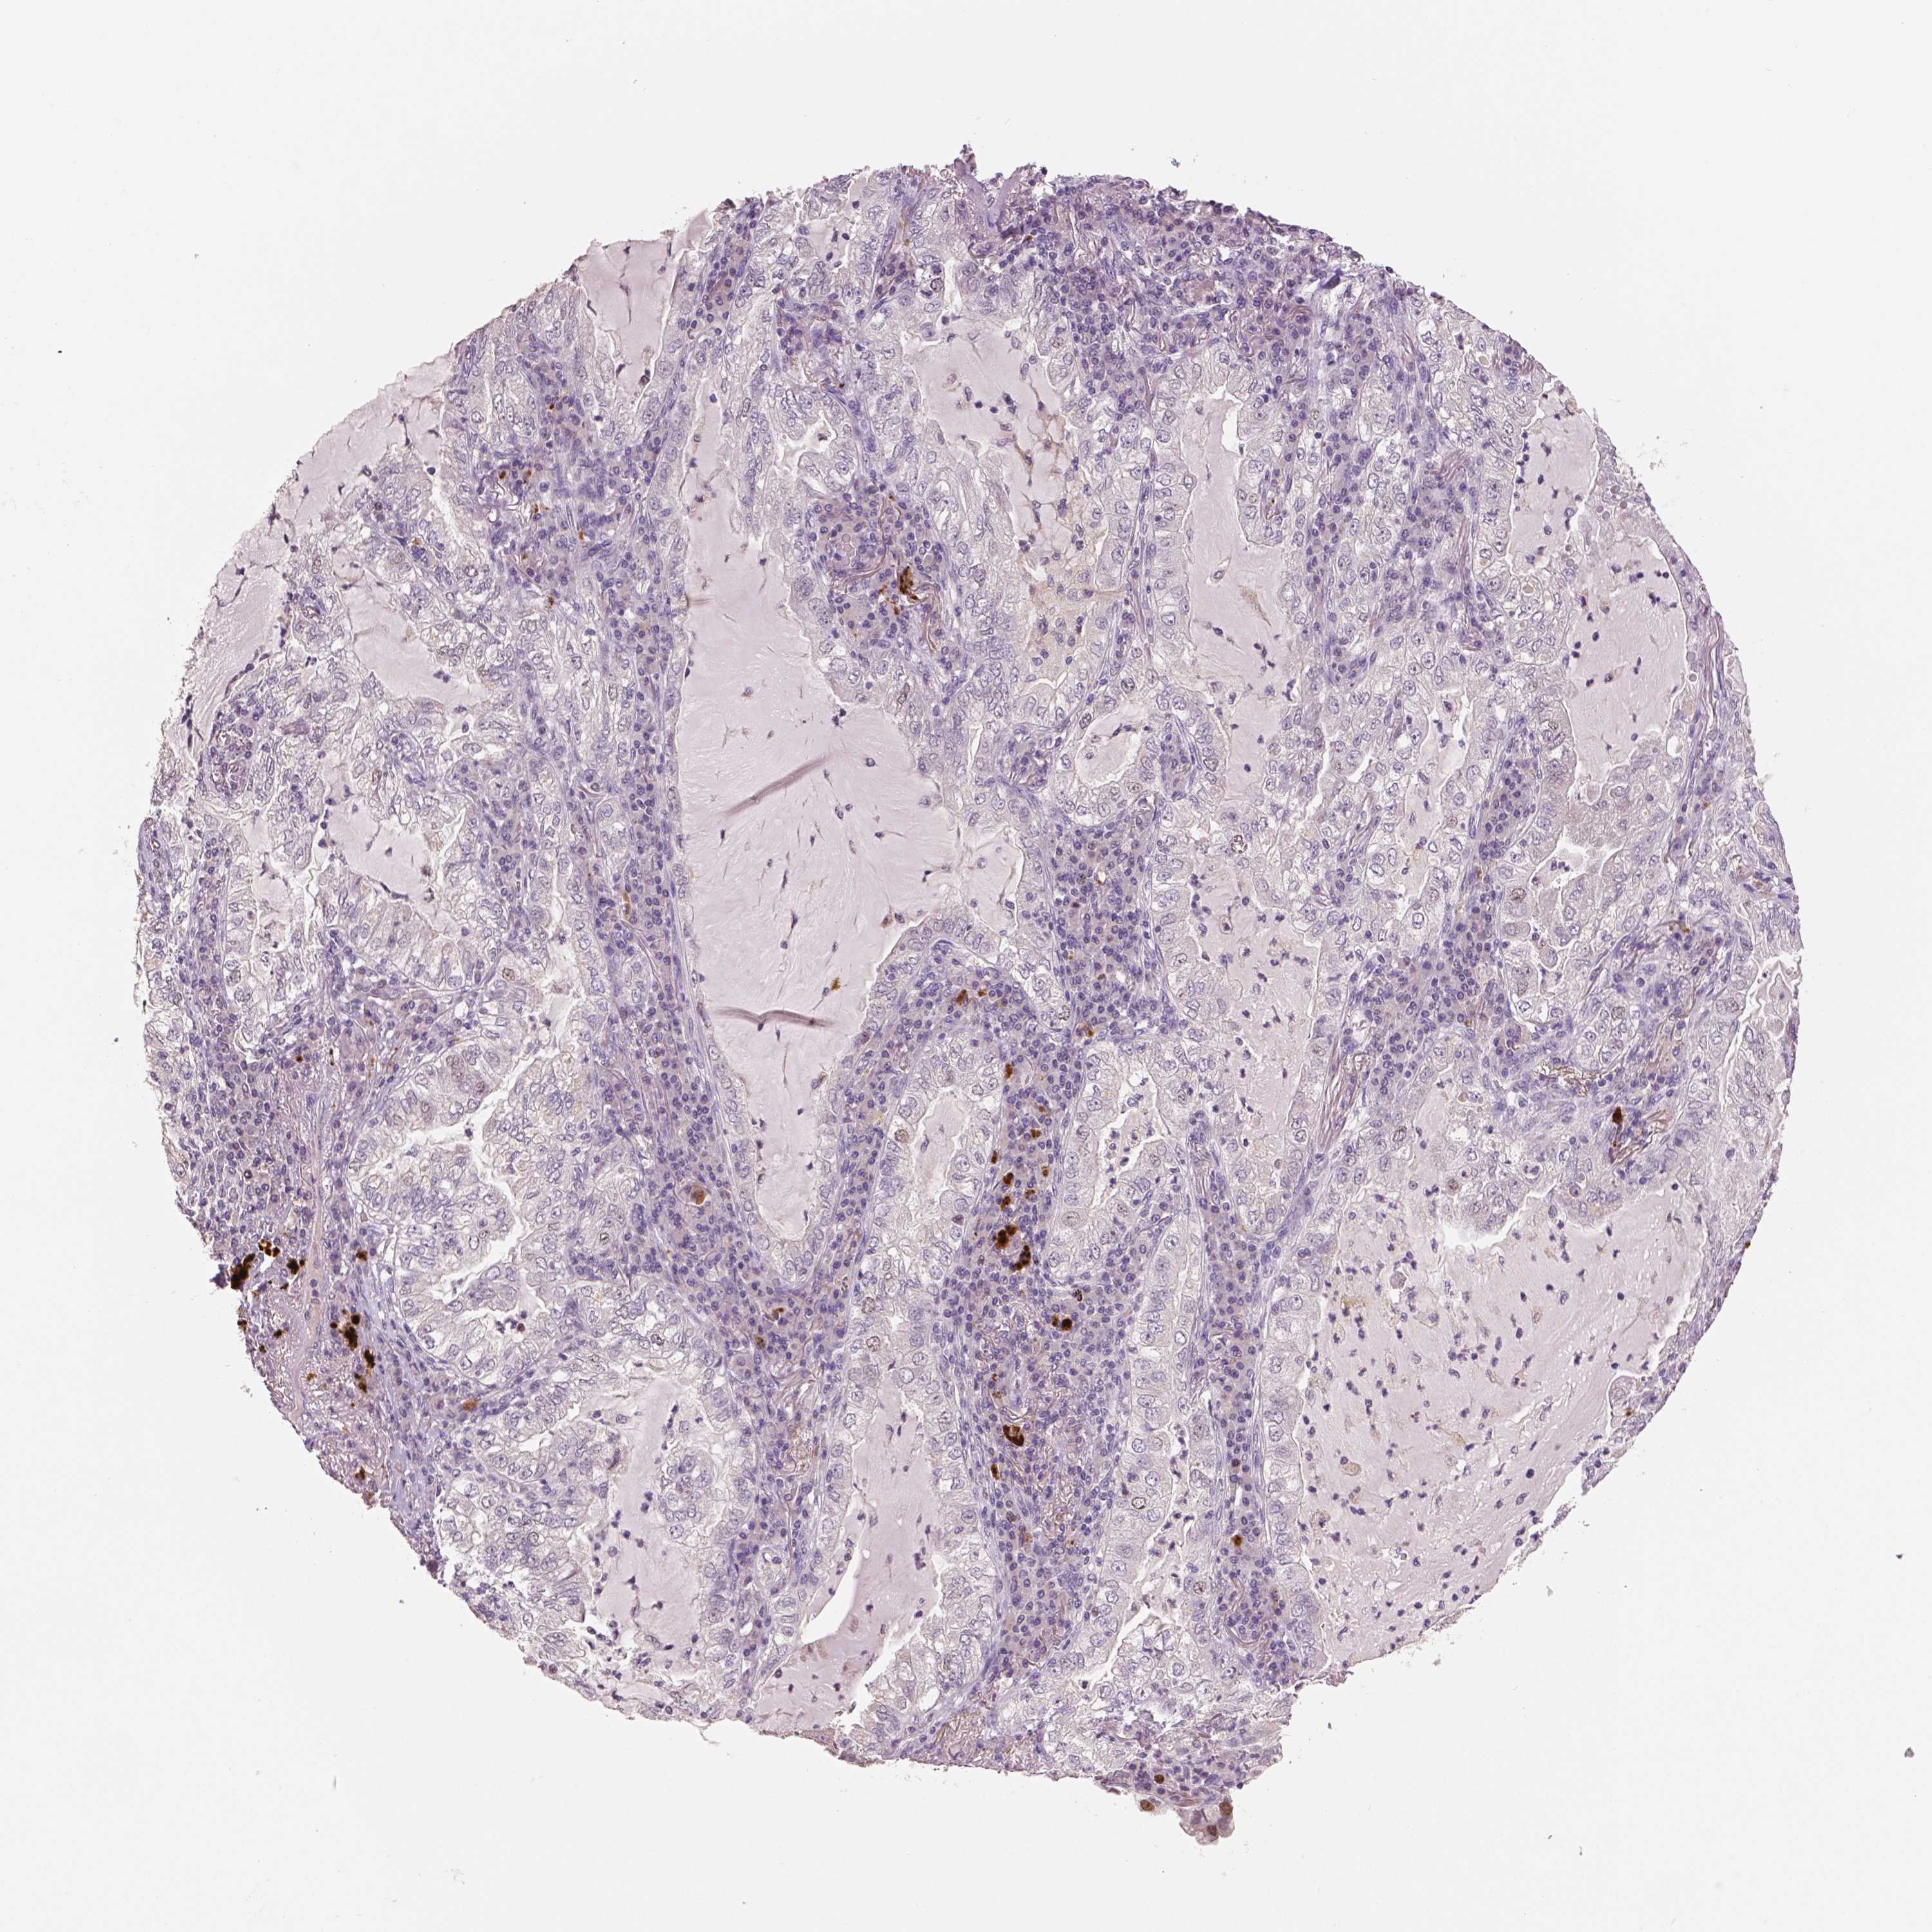

LUNG SQUAMOUS CELL CARCINOMA (TCGA) - Interactive survival scatter ploti

MKI67 is not prognostic in Lung Squamous Cell Carcinoma (TCGA)

: 13.48